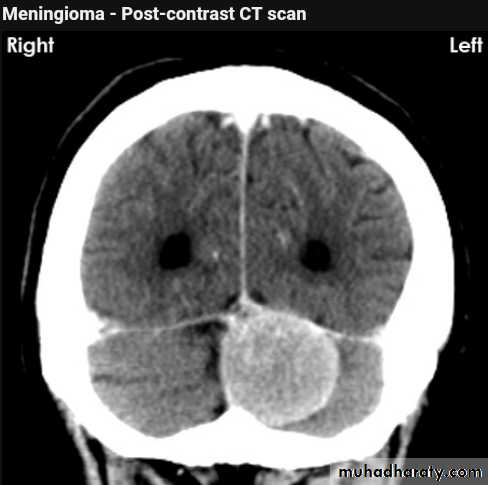

Meningioma

Benign tumor arise from the arachnid cells of the meningeal covering of the brain are most common primary intracranial neoplasm

Usually present in middle age female

it is well defined extra axial , located mainly at the convexity of the skull periphery

rounded or sessile , plaque like , specially the tumor arise from the cribriform plate , or those arise from the petrus bone , planum spheniodale , or from skeleton of the pituitary fosse .

CT finding

meningioma presented as isodense area or slightly hyper density area with surrounded crescent of hypo density ( csf cap ) post contrast injection the lesion enhance homogeneously with enhancing Dural tail .

20 % show calcification

hyperostosis & thickening of the near by bony part of the skull & diplioc space .

it may be associated with little or no peri focal edema .

if the lesion associated with central necrosis with large perifocal edema meningio sarcoma should be excluded .